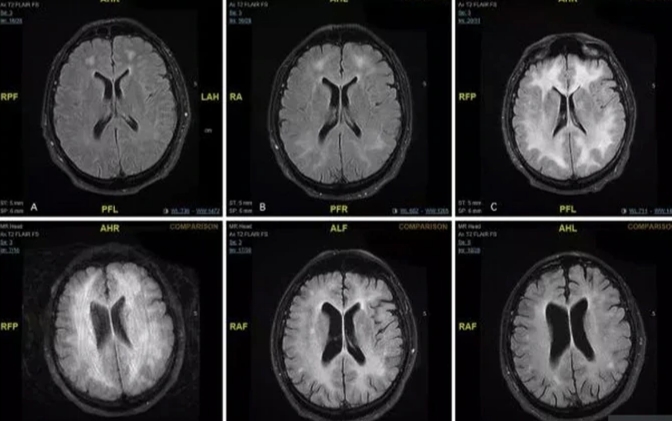

Las imágenes muestran cómo la droga puede ‘carcomer’ el cerebro de un consumidor, dejándolo con discapacidades y, en el peor de los casos, muerto

CIUDAD DE MÉXICO.- Las imágenes del cerebro obtenidas a través de estudios de resonancia magnética de un consumidor habitual de cocaína revelan el daño que la droga puede causar con el tiempo.

El paciente no identificado fue diagnosticado con una condición rara llamada leucoencefalopatía tóxica inducida por cocaína después de abusar regularmente durante años.

Los estudios fueron efectuados en el hospital de Msida, de Malta. Según los profesionales que atendieron al paciente que permanece internado, se trata de un hombre de 45 años que estaba confundido y se comportaba de manera extraña, antes de que los médicos se dieran cuenta de que padecía leucoencefalopatía tóxica inducida por cocaína.

Abdilla envió a su paciente para una resonancia magnética en su cerebro, que reveló daños en la sustancia blanca en el cerebro.

Un año después de ser ingresado en el hospital, el hombre regresó para un seguimiento. No había usado drogas durante un año, y aunque su escáner cerebral aún mostraba “cambios persistentes en la materia blanca”, las pruebas neurológicas eran normales.

Aparte de las anomalías, también detectaron que en la materia gris se refuerza el circuito de recompensa mientras que baja el tamaño de la materia blanca fuera del área de recompensa. Esto significa que aparecerían reforzadas las estructuras que tratan la gratificación en detrimento de las áreas que controlan procesos cognitivos como son la regulación de la propia conducta y la atención.